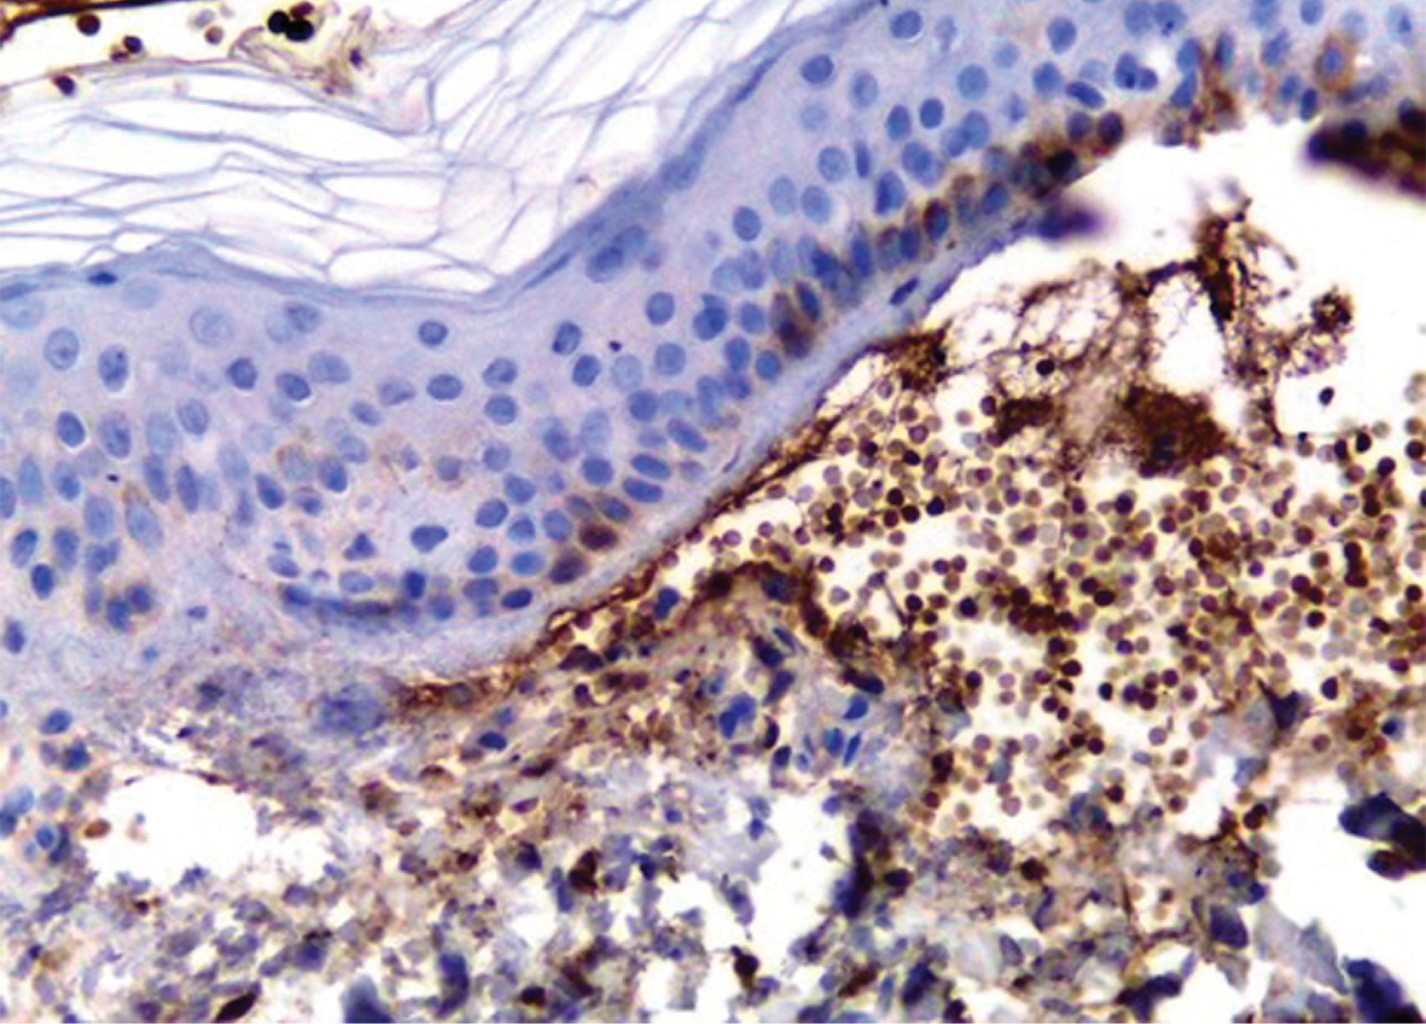

Se realiza biopsia de una de las vesículas, y con tinción de rutina se observó una ampolla subepidérmica (Figura 3) con restos de fibrina en el interior y presencia de polimorfonucleares (Figura 4), por lo que se solicita inmunofluorescencia e inmunohistoquímica para IgA e IgG (Figura 5), las cuales fueron reportadas como positivas, concluyendo que se trata de una enfermedad por IgA lineal.

Figura 5